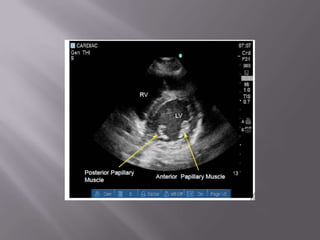

Ferramenta não apenas diagnóstica como de monitorização  Fundamental na abordagem do choque e da dispnéia  Permite em segundos descartar embolia pulmonar e tamponamento cardíaco como causas do choque  Usado na PCR – determinar causa reverível – durante a checagem do Pulso!  Transtorácico ou Transesofágico?